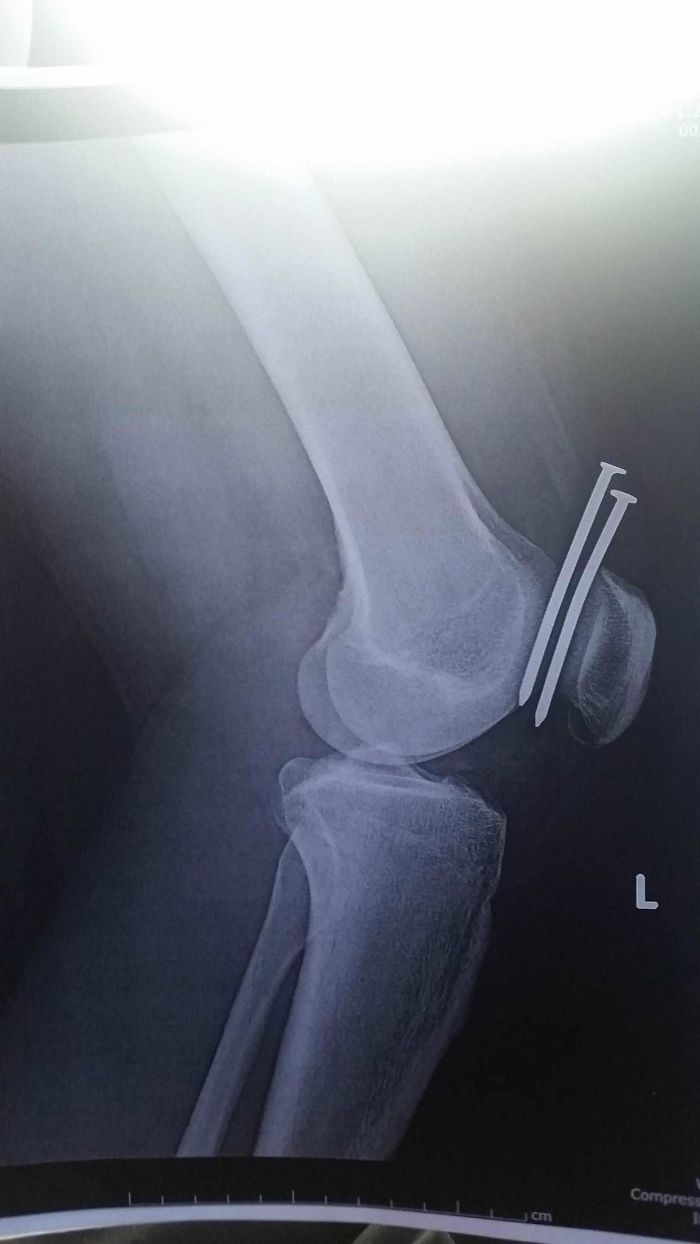

#34 This Guy Had Two Nails From A Nail Gun Hit His Leg, And They Both Missed His Femur And His Kneecap

Image source: ILLMATIC1994